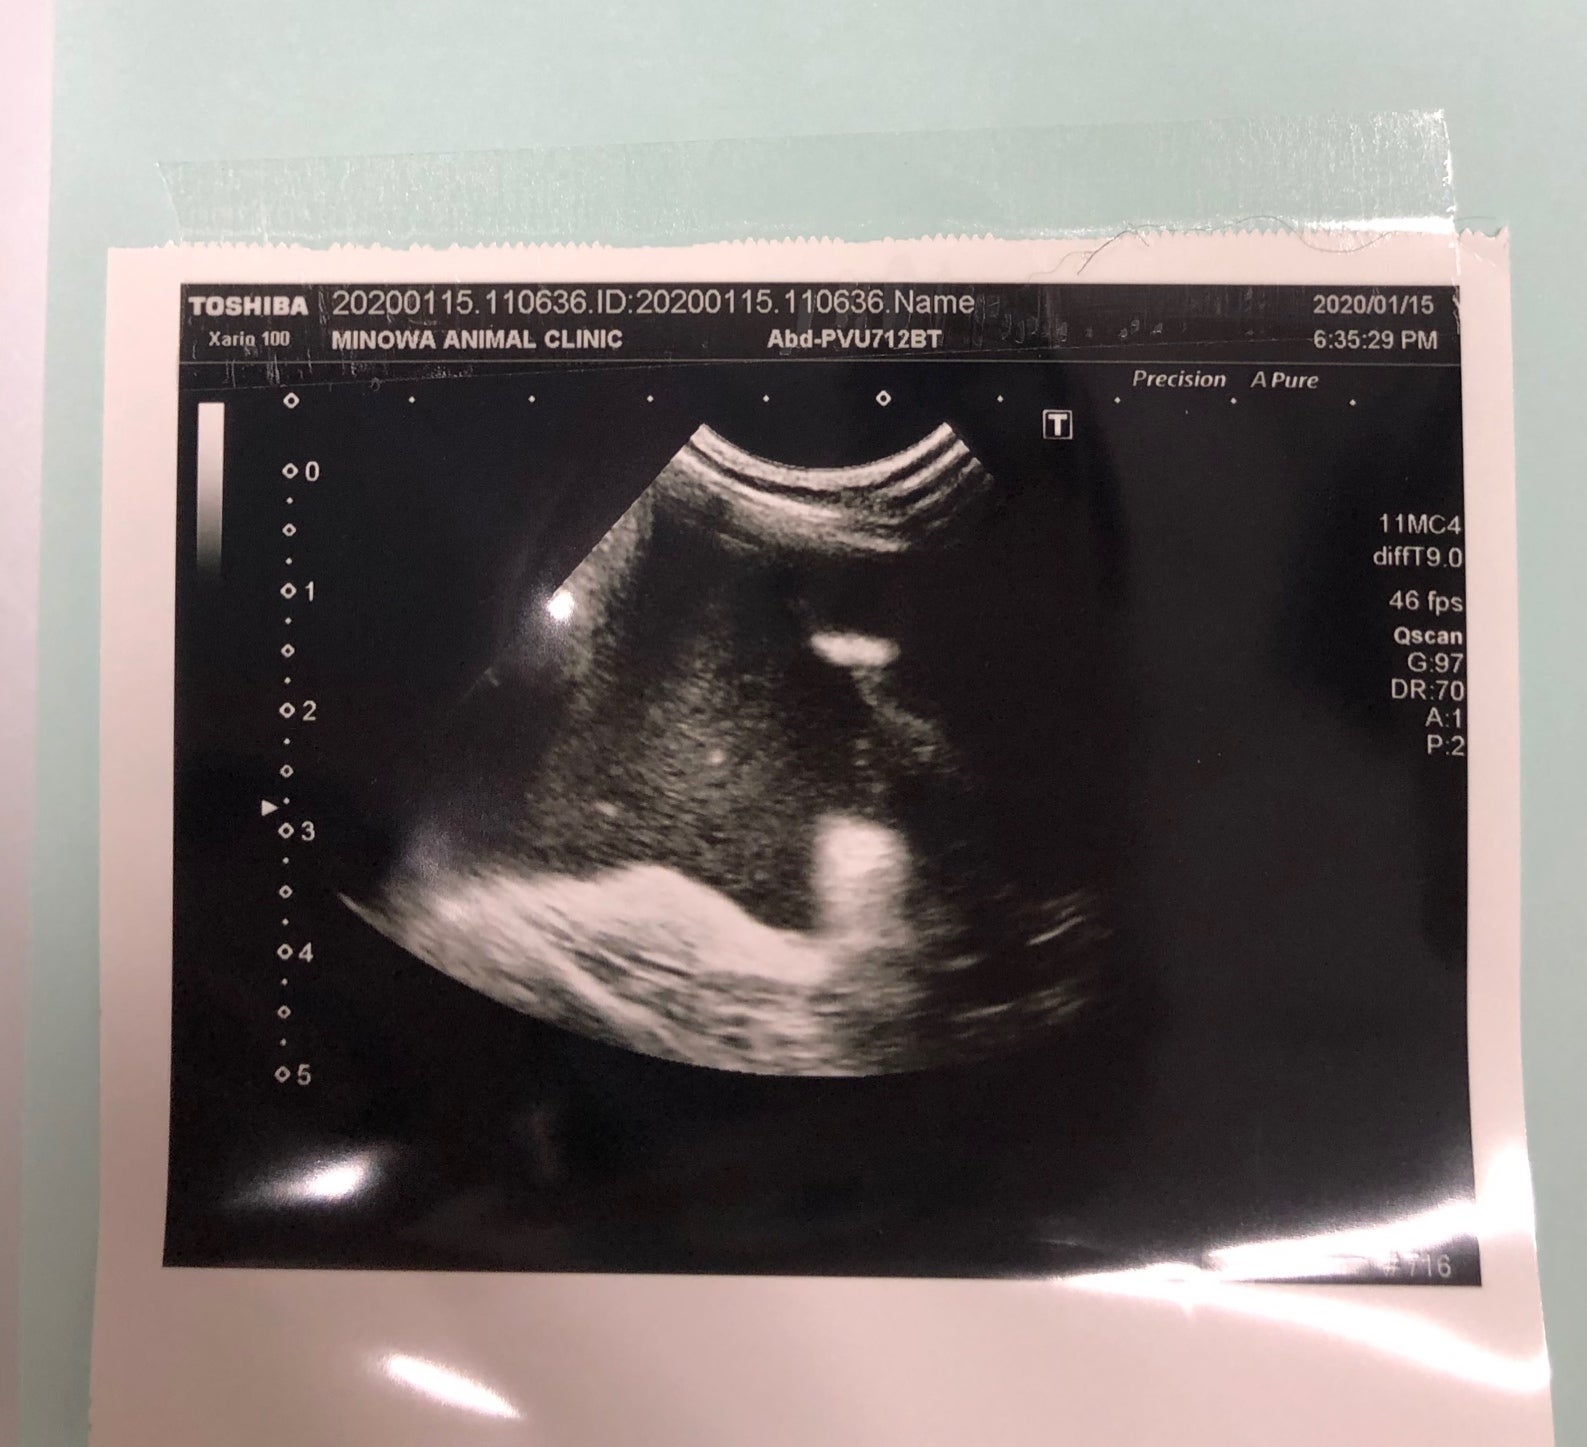

マロはウエットタイプで、初回診療時既に少量の腹水が溜まっていることが確認されました。

(こちらは腹水中のウイルス検査結果です)